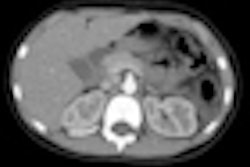

SABR -- sometimes called stereotactic body radiotherapy, or SBRT -- refers to a method of treating the tumor with a targeted high-energy radiation beam to damage tumor cell DNA and kill the cancer cell. It was first used in the Netherlands at the VUMC in 2003. The researchers used the Dutch National Cancer Registry to examine survival data for three defined periods: the three-year period before it was introduced, the three-year period while it was becoming available at other Dutch centers, and the three years when it was available nationwide, according to Dr. Suresh Senan, radiation oncologist at VUMC, who led the study based on nationwide data.